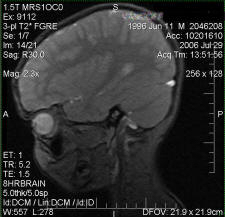

MRI

MRI, or Magnetic Resonance Imaging, takes advantage of the fact that different chemical elements respond differently in rapidly changing magnetic fields. Since different chemical elements are associated with different tissues in the body, it is possible to form medical images. Because this technique requires high-intensity magnetic fields, the equipment is large and expensive. The basic idea was first demonstrated in the 1940s by Felix Bloch at Stanford and, independently, by Edward Purcell at Harvard. It was not until the 1970s, however, that the technique became practical for human use. One of the leading developers, Raymond Damadian, formed a company to produce MRI machines, and they began taking orders in 1980. By the end of the decade thousands of MRI machines were in use in hospitals worldwide.